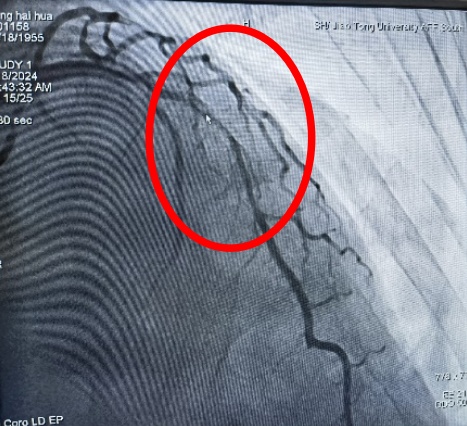

近日,奉贤区中心医院心血管内科开展了奉贤区首例震波球囊术,为复杂冠脉钙化病变再添新武器,进一步开启奉贤区冠脉复杂病变治疗新篇章。 患者张某,69岁,有高血压、糖尿病病史10多年,最近出现不稳定型心绞痛,收住院后择期行冠脉造影检查,造影结果提示:左前降支近段至中远段95%严重狭窄,IVUS(血管内超声)提示360°环形钙化。乔增勇主任团队尝试球囊预扩张,普通球囊+高压球囊反复扩张10余次均不能撼动钙化斑块一丝一毫。乔增勇主任意识到再这样继续扩张下去可能会导致冠脉夹层甚至冠脉穿孔等严重并发症。 高压球囊扩张,呈“狗骨头”效应(箭头处) 在医院的统筹协调下,震波球囊很快到位。乔增勇主任、葛广豪主任医师及杨立国主治医师密切配合,先是利用震波球囊在钙化病变处进行5组脉冲治疗,待钙化的组织被“震碎”后,可见震波球囊完全膨胀,IVUS证实360度“戒指样”钙化环被震开,再次高压球囊扩张后在病变处进行支架植入,术后IVUS进一步证实左前降支架膨胀贴壁好,恢复完全通畅状态,患者病灶得到解除。 术前(前降支95%弥漫性狭窄) 术后狭窄消失 震波球囊技术 震波球囊技术又称血管内冲击波碎石术,是利用设备将电能传递到发射器上,通过发射器产生声波压力波,将球囊内液体汽化,借助气化的液体对血管内膜、中膜的钙化组织进行隔空“敲裂”。 优点: 1.针对性强,只针对钙化组织,对正常血管组织无影响; 2.冲击波治疗后可增加血管顺应性,让血管“恢复年轻态”; 3.有些钙化病变需要震波球囊联合旋磨及切割球囊等“组合拳”方能解决。 奉贤区中心医院心血管内科针对复杂冠脉钙化病变,根据病变特点已成功开展旋磨术,切割球囊及棘突球囊等技术。目前再添新武器“震波球囊技术”,为奉贤区复杂冠脉病变治疗插上新的翅膀,让区内复杂冠脉病变患者不出奉贤即可享受市区三甲医院同质化优质医疗服务。